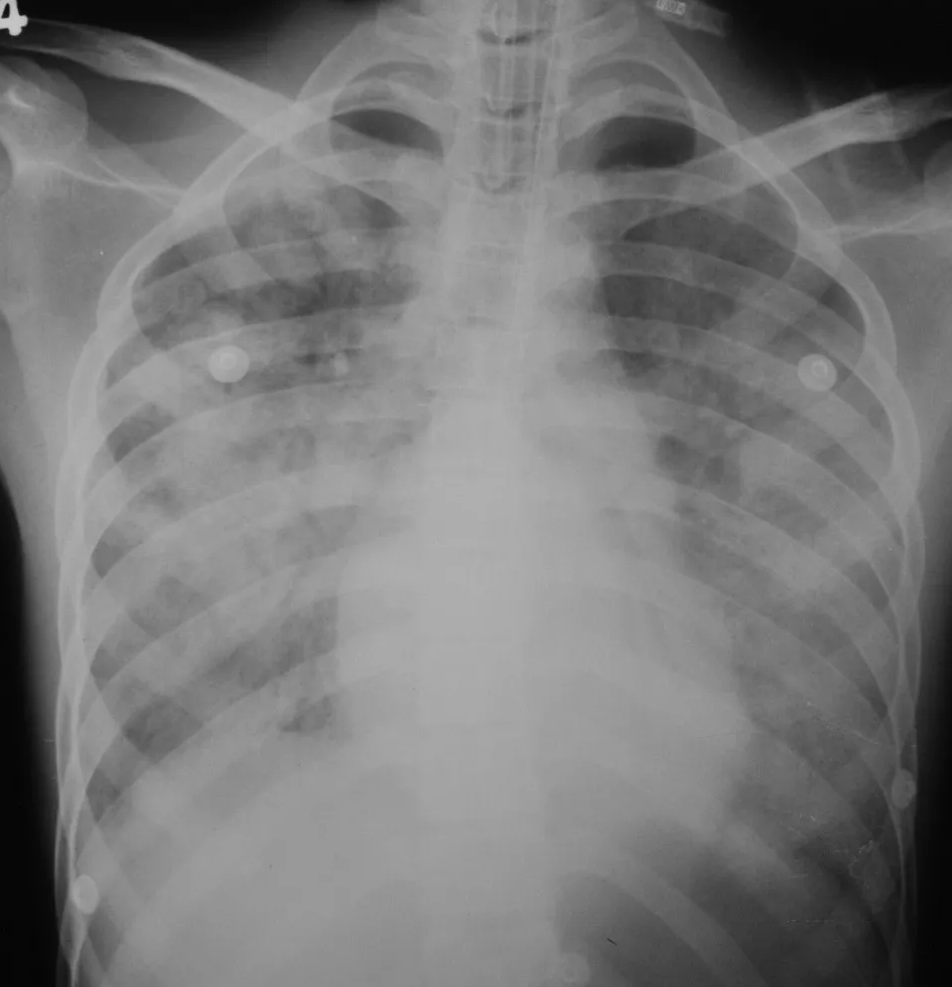

폐렴이 있는 경우, 흉부 X선 사진에서 확산성 폐포 음영이 나타날 수 있다.[34]